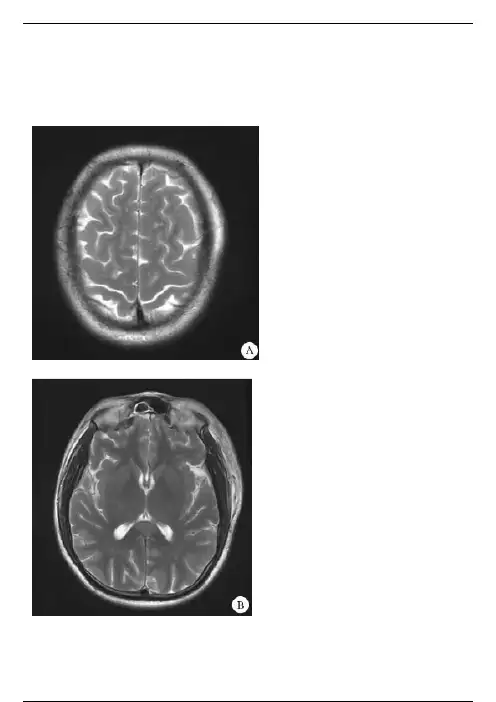

病史摘要(2)男性,44岁。

车祸伤后持续性昏迷16小时。

【影像学检查】【影像学表现】MRI平扫横断位T1WI(图A)、T2WI(图B)和T2 -FLAIR(图C)显示双侧半卵圆中心多发点状、条片状长T1、长2信号;SWI(图D)显示双侧半卵圆中心斑点状低信号。

【影像学诊断】弥漫性轴索损伤。

【最后诊断】弥漫性轴索损伤。